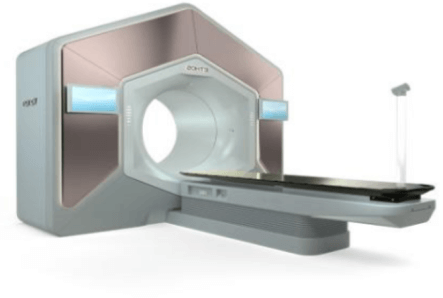

В процессе лечения мы используем новейшие медицинские технологии и оборудование. Для вас работают профильные специалисты, имеющие практический опыт и периодически повышающие квалификацию.

Мы предоставляем помощь на всех этапах. Вам доступна противоопухолевая лекарственная терапия с применением разных схем сложности, лучевая терапия, хирургия. Мы принимаем участие в программе обязательного медицинского страхования. Поэтому онкология по ОМС в Москве в может быть пролечена в нашей клинике.